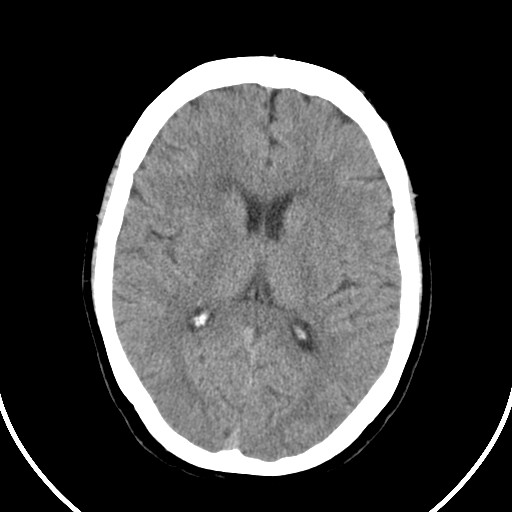

标题: CT21850:女,56岁,右中指淤肿,右手麻痹1天

女,56岁,右中指淤肿,右手麻痹1天

右侧侧脑室旁脑白质腔隙性脑梗死。

右侧基底节多发小梗塞

作者: huangyinshan    时间: 2009-8-25 15:37

右基底结区腔梗

右侧基底节区腔隙性脑梗塞

右侧基底节多发腔梗!

双侧侧脑室额角旁对称性略低密度影,边缘模糊,无占位效应,考虑轻度脑白质稀疏症(病人有高血压吗).,右枕叶低密度影多为伪影,不放心薄扫一下.

考虑脑白质病。

考虑脑白质病

右枕叶条状低密度影不应该忽略可能极具意义